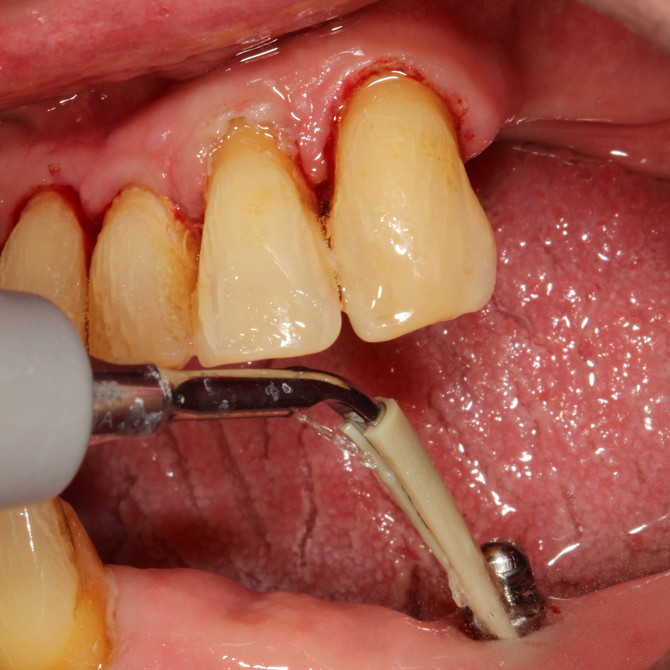

Metallfreier Spezial Aufsatz aus hochwertigem Kunststoff (PEEK) entfernt mühelos Plaque und Zahnstein von Implantatoberflächen und Restaurationen aus Metall oder Keramik

Keine Beschädigung oder Abrasion von Titanoberflächen

Reinigung unter Spülung und Speichelabsaugung

Ultraschallaufsatz OHNE Spezial Kunststoffspitze – zur supragingivalen Entfernung von Konkrementen MIT Spezial Kunststoffspitze – für die schonende Implantatprophylaxe